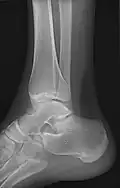

- Ankle - AP/Mortice and Lateral

-

Ankle - frontal -

15 degrees internal rotation -

Lateral (this one a bit suboptimal by not seeing straight through the ankle joint) -

Lateral oblique (to visualize the posterior border of the tibia)